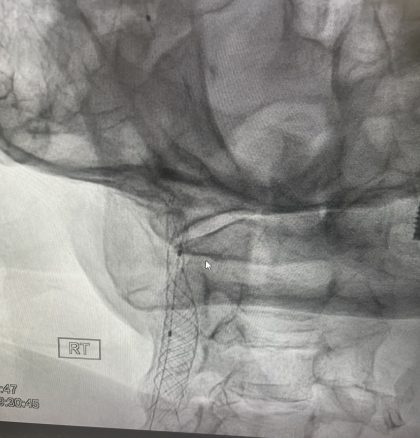

הערה: פרטי המטופל טושטשו לשמירה על חיסיון רפואי. הרקע: נורות אזהרה מהבהבות דוד (שם בדוי), בן 78, הגיע למרפאה של פרופ' מיכאל יונש לאחר שחווה פעמיים "מסך שחור" שירד על עינו הימנית למשך דקה ונעלם. תופעה זו, הנקראת Amaurosis Fugax, היא סימן קלאסי ומדאיג לכך שקריש דם קטן חוסם זמנית את עורק הרשתית – אירוע…

סיפור מקרה: הצלת ראייה ומניעת שבץ בגיל 78- הטיפול בהיצרות של 95%

ההחלטה כיצד לטפל בהיצרות משמעותית בעורק הקרוטיס היא אחת ההחלטות הרפואיות החשובות. בעבר, האופציה היחידה הייתה ניתוח. כיום, הטכנולוגיה מאפשרת טיפול זעיר-פולשני באמצעות צינתור. מהו ניתוח קרוטיס  ?(Endarterectomy) בניתוח הקלאסי, המנתח מבצע חתך בצוואר, פותח את העורק ומקלף ממנו את הרובד הטרשתי החוסם. זהו הליך מוכח ויעיל, אך הוא דורש הרדמה (לרוב כללית או מקומית…